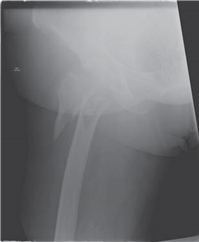

What does this radiograph show and how would you classify this fracture?

There is a displaced intracapsular fracture of the right neck of femur. I would describe this as a Garden IV fracture as there is complete displacement. Clinically the most important classifi cation is simply between displaced and undisplaced fractures.